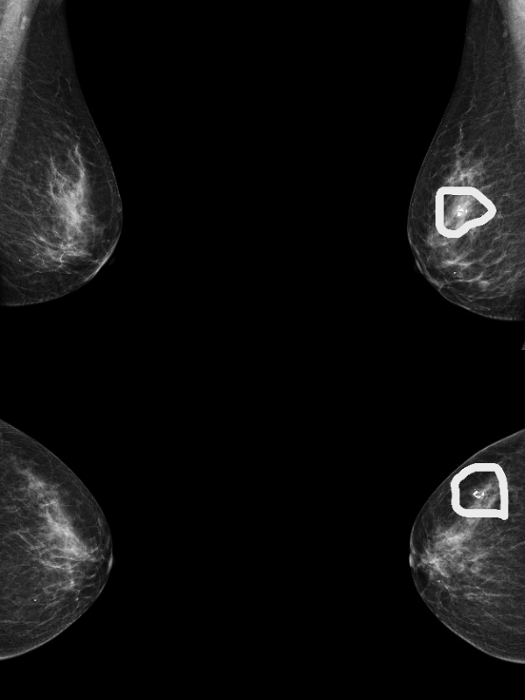

患者A钼靶显示“正常”,但超声发现囊肿和实性结节(如图1、2);

图2 患者A的超声表现图:(粗箭头处)乳腺囊肿,表现为无回声区;(细箭头处)乳腺实性结节,表现为低回声